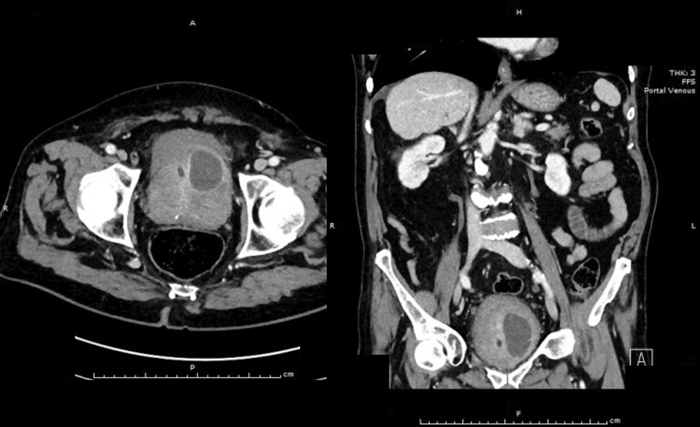

A 76-year-old diabetic man with a long-term catheter presents to the Emergency Department with rigors and non-specific abdominal pain. He has an elevated white cell count (WCC) and C-reactive protein (CRP). An abdominal and pelvic CT scan was arranged. Selected CT images are shown below:

There is a peripherally enhancing collection in the left antero-superior aspect of the prostate extending into the bladder base, approximately 40mm x 30mm. Diagnosis: left-sided prostatic abscess.